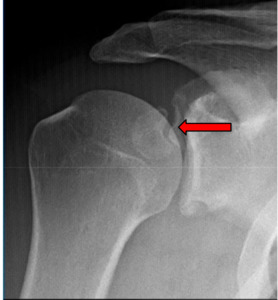

Imaging: Preoperative imaging included standard radiography using anteroposterior, Grashey, scapular Y and axillary views (Fig 1-2). After determining the presence of a coracoid fracture, advanced imaging was conducted via computed tomography with addition of 3-dimensional reconstruction. CT imaging was suggestive of a type 2 coracoid fracture nonunion (Fig 3) which was then further verified with no enhancement with T2 MRI sequences (Fig 4).

Operative Results: The patient was positioned supine in beach chair position with the assistance of a mechanical arm holder. A 30 degree scope was used during the entire procedure without need to switch to a 70 degree scope due to multiple portal use. The first portal was established as a standard posterior viewing portal (A) followed by a standard anterior portal (E) under direct visualization, Figure 5 demonstrates portal selection. From the anterior portal a thorough debridement via arthroscopic shaver and radiofrequency ablation was undergone of the rotator interval to the tip of the coracoid process (Figure 6). After visualization of the lateral coracoid was obtained, the radiofrequency ablator was used to clear the soft tissue until the coracoclavicular ligament is encountered at the anterolateral aspect of the coracoid (Figure 7). Unlike the arthroscopic Latarjet technique, the CC ligament does not need to be fully released but can be partially released for visualization. The D portal (anterolateral portal) is then made under visualization from the posterior portal and viewing is moved to the D portal. The ablator is then moved to the anterior portal to allow for clearing of the superior coracoid. The purpose of the switch of viewing to the D portal is increased visualization of the tip of the coracoid, conjoined tendon, and an en face view of the glenoid. Extra care should be undertaken when moving medially to the fracture site to avoid damage to the axillary nerve, blunt dissection can be done with the ablator to identify the axillary nerve. Next, through the D portal, the I portal (anterior inferolateral portal) can be established under direct visualization in line with the conjoined tendon for placement of the K-wire and cannulated screw. Through the I portal the ablator is inserted to remove a small portion of conjoined tendon for the K-wire insertion site and future cannulated screw. Placement of a blunt trocar is then inserted into portal E and fracture mobility is assessed. We then moved to creating portal H, insertion of a spinal needle under direct visualization in line and superior to the coracoid process. The ablator can then be used through portal H to debride the built up non union fibrous soft tissue (Figure 8). To get a full and adequate debridement of the fibrous tissue, a small amount of the pectoralis minor tendon may need to be released depending on the location of the fracture as it may act as a deforming force. After adequate debridement, a shaver or burr is used to debride bone edges to bleeding bone. A drill guide is then inserted through portal I at the tip of the coracoid process (Figure 9) while a probe is inserted through portal H to reduce and stabilize the fracture site for K wire insertion. The K-wire can be used to joystick the fracture as well while in the distal fragment. Once reduction is achieved the k wire is inserted into the proximal fragment, but not advancing too far to put the suprascapular nerve at the suprascapular notch. A cannulated drill is then passed over the K-wire in both proximal and distal fragments. A 4.5 cannulated screw is then inserted over the guidewire (Figure 10). A blunt trocar can be placed within the H portal to allow the operator to prevent/minimize rotation of the fragment during insertion of the cannulated screw. Post operative care included postoperative radiographs for reduction assessment and screw length (Figure 11). Patient placed within an abduction sling for 6 weeks, gentle range of motion was initiated at 2 weeks post op. After fracture union, the patient should return to normal activities at approximately 3 months post op.